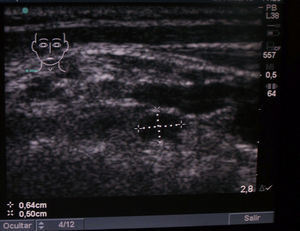

Se observó una imagen hipoecogénica ovoidea en topografía compatible con una glándula paratiroidea en 10 casos, y 2 o más (bilaterales) en 14 casos (figs. 1-2). El tamaño fue menor de 1cm en 10 pacientes, entre 1 y 1,5cm en 11, y mayores de 1,5cm en 3 casos (1,6; 1,7 y 1,8). Tenían ecografías previas en otros centros informadas como normales 9 pacientes. En la evolución se repitió la ecografía en 13 de nuestras pacientes, hallando imágenes similares a la primera en todas. La calcemia y la PTH fueron normales en 23 pacientes, con seguimiento en casi todas. La 25-hidroxivitaminaD se midió en la mitad de los casos, siendo mayor de 30ng/ml en un tercio, entre 20 y 30ng/ml en un tercio, y menor de 20ng/ml en otro tercio. No hubo relación entre tamaño o número de imágenes posiblemente paratiroideas y nivel de vitaminaD. Una de ellas, de 46 años, con una imagen de 6mm, tuvo PTH levemente elevada con calcemia normal, con vitaminaD en rango deseable (38ng/ml). En el seguimiento se elevó la calcemia, y un centellograma con MIBI fue positivo, por lo que fue intervenida quirúrgicamente con resultado de un adenoma paratiroideo.